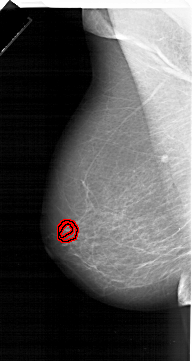

A_1207_1.LEFT_MLO

LEFT_MLO LINES 6496 PIXELS_PER_LINE 3451 BITS_PER_PIXEL 12 RESOLUTION 43.5 OVERLAY

FILE: A_1207_1.LEFT_MLO.OVERLAY

TOTAL_ABNORMALITIES 1

ABNORMALITY 1

LESION_TYPE MASS SHAPE IRREGULAR MARGINS SPICULATED

ASSESSMENT 5

SUBTLETY 1

PATHOLOGY MALIGNANT

TOTAL_OUTLINES 2

BOUNDARY

CORE